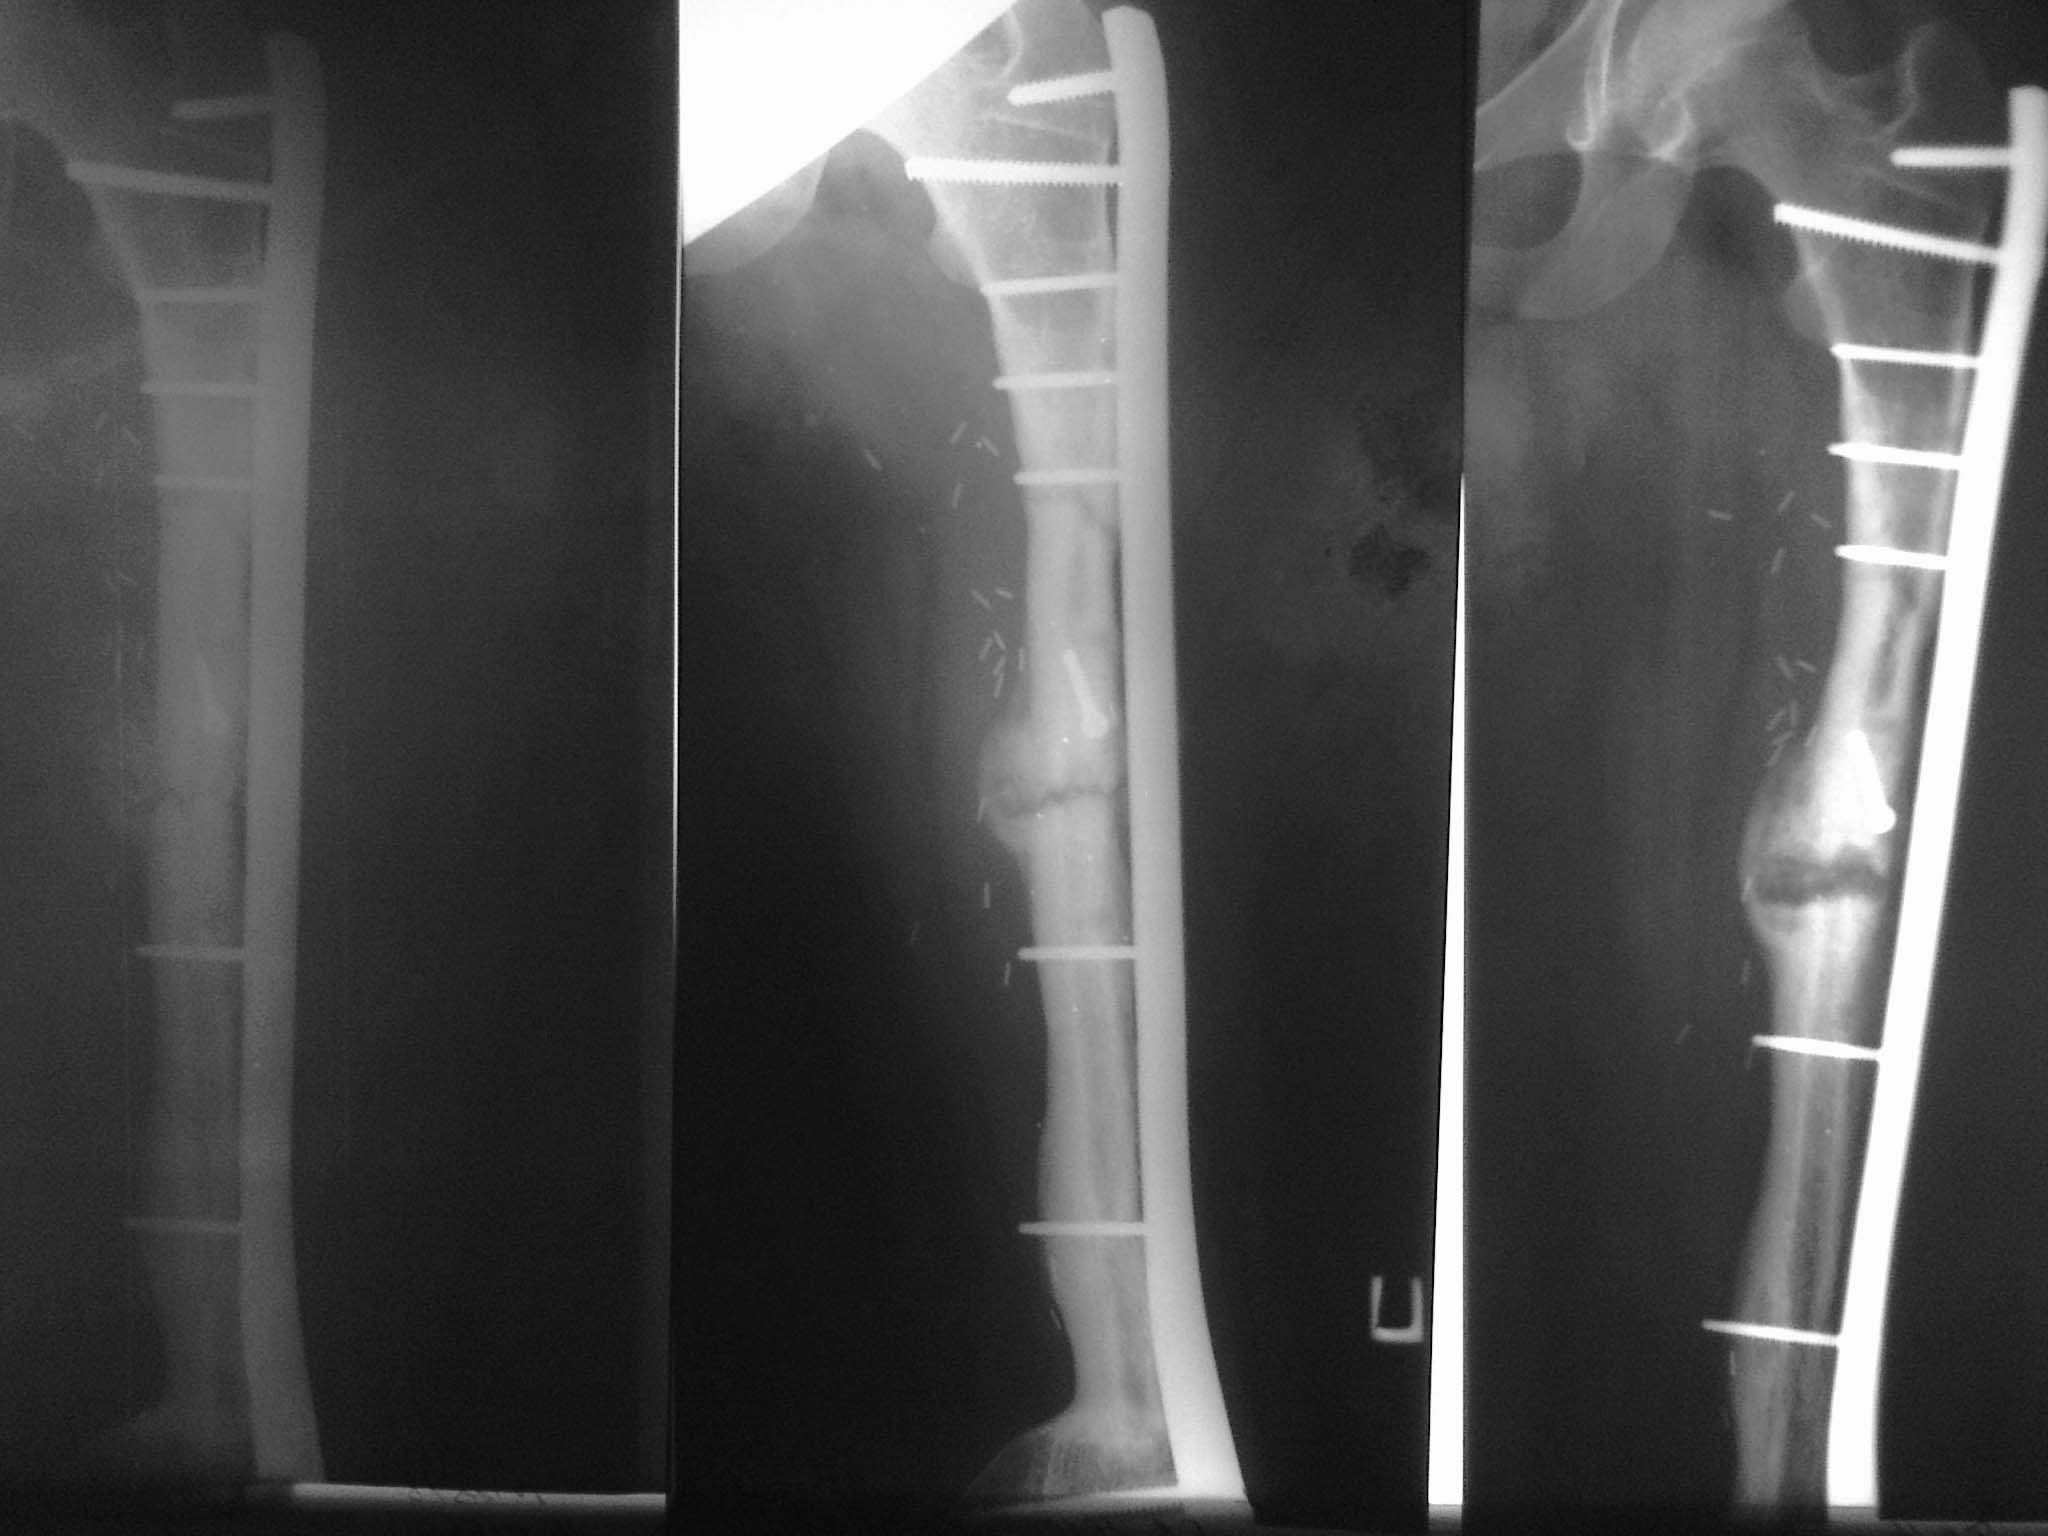

Уважаемые коллеги, нужен совет. Девочка, 18 лет, остеогенная саркома 2010 год, резекция,

замещение свободным васкуляризированным трансплантатом малоберцевой кости с

остеосинтезом L-образной пластиной.

Пластина удалена в 2011 году после консолидации концов трансплантата и проксимальных и

дистальных концов бедренной кости (хотя нестабильность конструкции, миграция винтов

имело место быть. В 2012 году несколько переломов трансплантата, лечение консервативное.

Сентябрь 2012 после очередного перелома открытая репозиция, костная аутопластика

кортикально-губчатым трансплантатом из крыла подвздошнй кости с МОС пластиной с угловой

стабильностью. Интраоперационно - без особенностей. В период динамического наблюдения на

фоне образования костной мозоли отмечается литическая деструкция концов костных отломков

в зоне перелома (снимки - 1 мес, 2.5 мес и 3.5 мес после операции. Что это? Метастаз? Откуда (из

крыла?) Нестабильность(признаков нет..)? Какую тактику посоветуете? Спасибо.